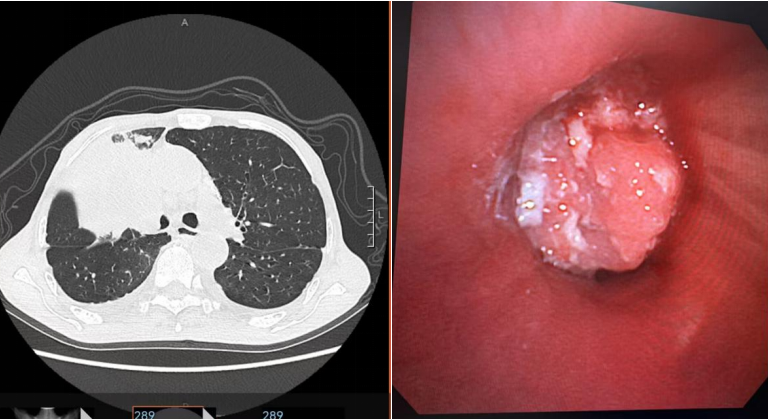

12月13日,思南县人民医院呼吸与危重症医学科在浙江大学医学院附属邵逸夫医院呼吸与危重症医学科张冀松博士的指导下,首次完成“支气管镜下肿瘤切除术及内科胸腔镜检查”。该技术通过支气管镜引导,将特制电圈套器精准置入患者气道肿瘤部位,通过电圈套器将气道肿瘤切割,快速解除呼吸道梗阻,成功救治一名因支气管肺癌引起呼吸困难的患者。标志着思南县人民医院呼吸介入诊疗水平迈入新高度,填补了院内气道肿瘤微创介入治疗的空白。

患者王先生(化名),79岁,因“咳嗽、咳痰及气促2月”入院。影像学检查显示右肺上叶支气管占位,右肺上叶阻塞,右肺通气功能严重受阻,活动后明显气促。气管镜下见右主支气管远端被肿瘤几乎完全阻塞,短期全身静脉化疗不能及时解除患者呼吸困难症状,经科室讨论后,建议先行支气管镜下肿瘤切除术开通患者气道,再行静脉化疗。